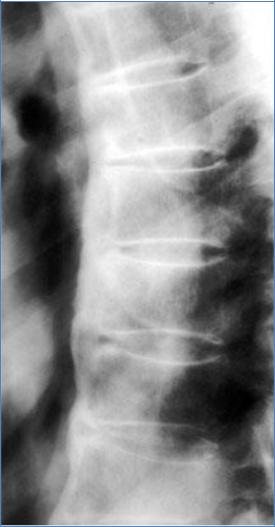

Болезнь Бехтерева

Анкилозирующий спондилартрит – заращение всех суставов позвоночника.

Обызвествление продольных связок делает такой позвоночник неподвижным.